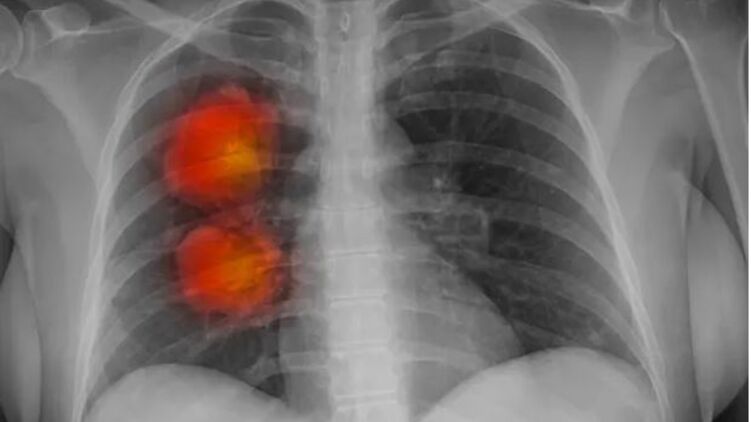

Инструмент искусственного интеллекта был разработан экспертами фонда Royal Marsden NHS, Института исследования рака в Лондоне и Имперского колледжа Лондона. Он может определить, являются ли аномальные новообразования, обнаруженные на КТ, злокачественными.

Команда использовала компьютерную томографию около 500 пациентов с большими узлами в легких для разработки алгоритма искусственного интеллекта. Этот метод может извлекать жизненно важную информацию из медицинских изображений, которые трудно заметить человеческому глазу.

Согласно первоначальным результатам, модель ИИ, по-видимому, точно идентифицирует раковые крупные узелки в легких.